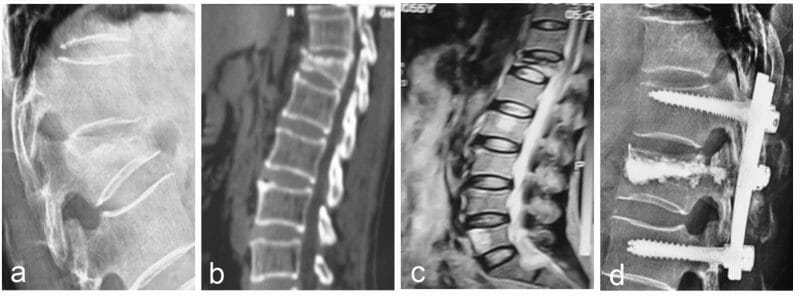

โดยทั่วไปโรคกระดูกสันหลังยุบมักวินิจฉัยได้จากภาพ X-ray อย่างไรก็ตามในผู้ป่วยบางรายที่ภาพ X-ray ไม่สามารถแสดงลักษณะกระดูกสันหลังยุบได้ชัดเจน อาจมีความจำเป็นต้องทำ MRI Scan เพื่อช่วยในการวินิจฉัยเพิ่มเติม

ในผู้ป่วยที่มีอาการปวดมาก มีอาการกดทับเส้นประสาท หรือมีการยุบตัวของกระดูกรุนแรง แพทย์อาจจำเป็นต้องพิจารณาการรักษาโดยวิธีผ่าตัด โดยมีตั้งแต่การรักษาโดยการฉีดซีเมนต์บริเวณที่กระดูกยุบ การผ่าตัดใส่สกรูเพื่อยึดดามกระดูก หรืออาจจำเป็นต้องทำทั้งสองอย่างร่วมกัน